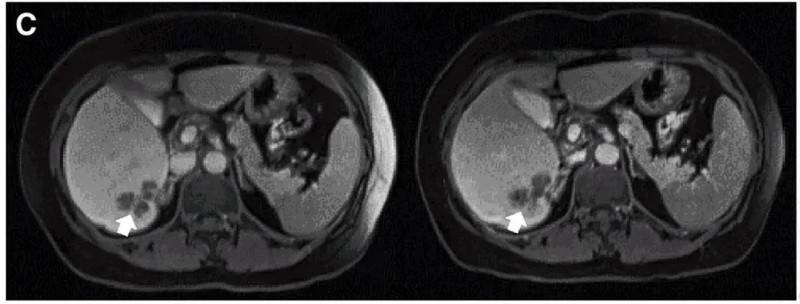

我国曾开展一项“CEA靶向CAR-T细胞疗法治疗CEA阳性结直肠癌的I期临床试验(NCT02349724)”。

结果振奋人心:10例既往治疗进展(PD)的患者中,7例治疗后达到病情稳定(SD),肿瘤直径仅轻微变化,其中2例稳定状态持续超30周(7.5个月)。值得一提的是,其中一个典型病例(P10患者)在接受DL4剂量CEA CAR-T治疗后,MRI证实其肝内一处病灶明显缩小(详见下图)。

▼P10患者在CAR-T治疗前(左图)、治疗4周后(右图)的MRI对比

▲图源“Molecular Therapy”,版权归原作者所有,如无意中侵犯了知识产权,请联系我们删除